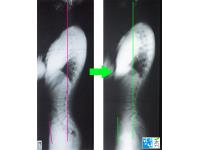

• 교정전후사진